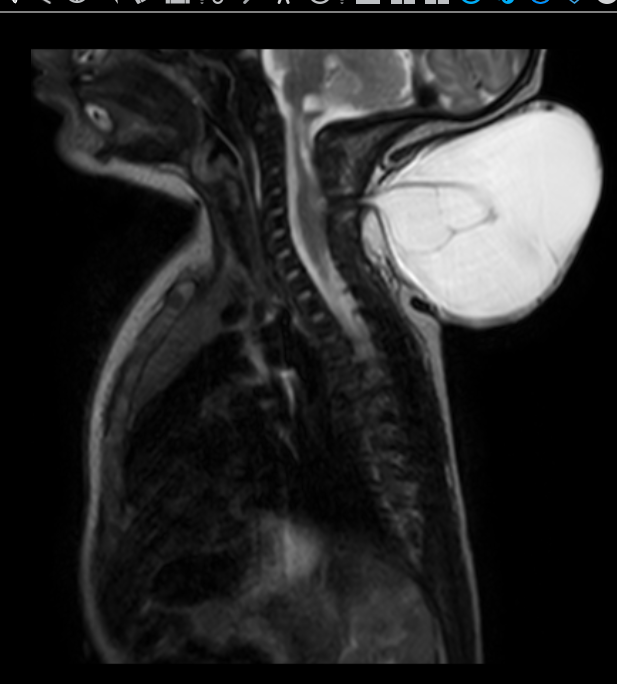

An MRI on the child, Priti Das (name changed on request), revealed a 10×10 cm in size swelling on the baby’s neck, which was tense and looked like it was about to give way. The swelling was too large and would affect growth of the child. If it ruptured, it could lead to a brain infection which could be life-threatening.

Cervical Myelomeningocele is a very rare condition characterised by a swelling in the back of the neck since birth due to improper development of the nervous system. The swelling was initially found on the foetus during a routine ultrasound. The child’s mother, a 28 year old bank employee working in Karnataka was then referred to Aster RV Hospital, J.P. Nagar for further treatment.